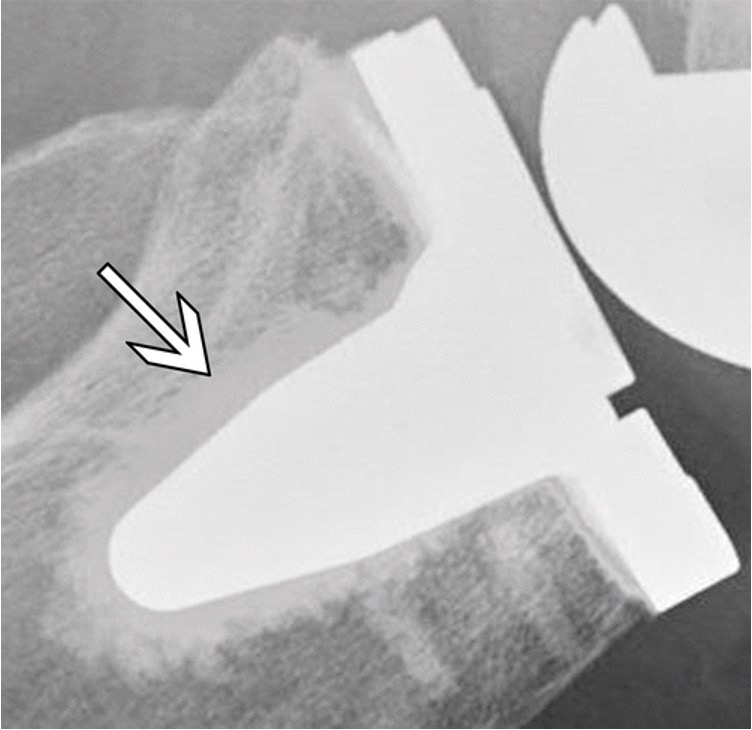

For CR, exposure indicator errors are likely unless at least 30 percent of imaging plate is exposed

Therefore, for tightly-colllimated views of digits, it is recommended that two or three views be taken on one imaging plate.

Use at least 1/3 of the CR plate for an exposure